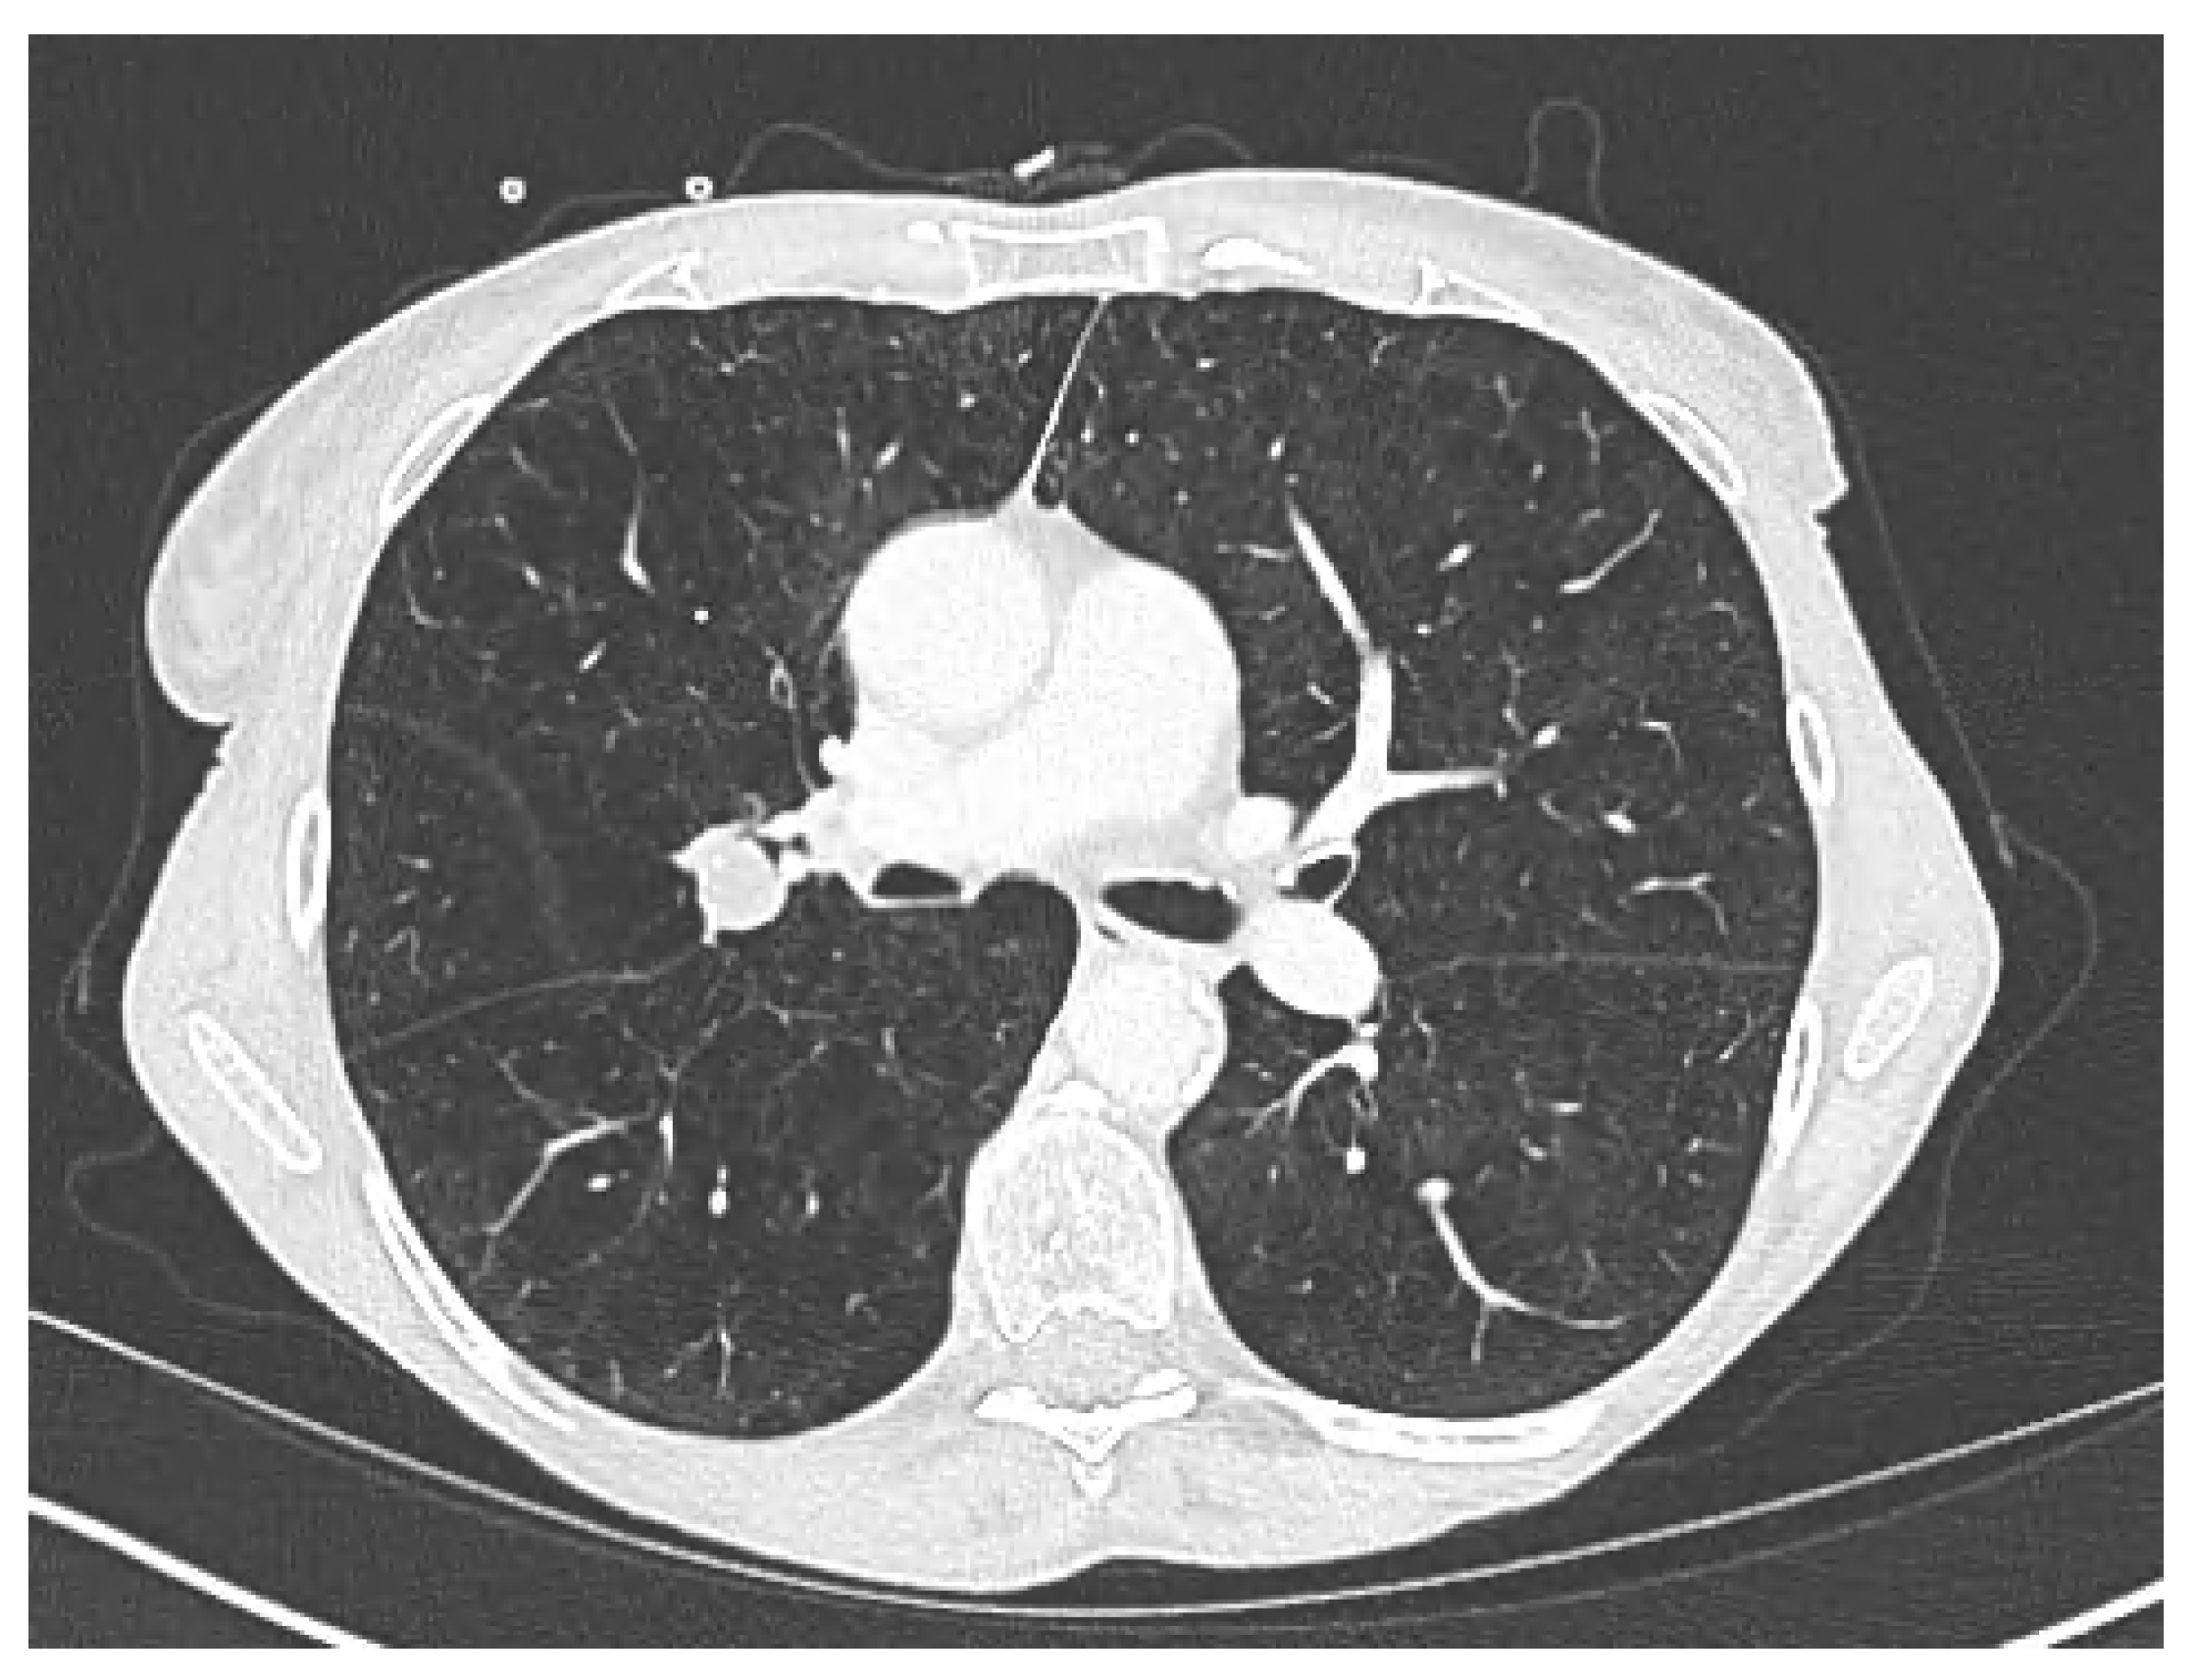

Lung Stereotactic Body Radiation Therapy in a Patient with Severe Lung Function Impairment Allowed by Gallium-68 Perfusion PET/CT Imaging: A Case Report

Lucia, F.; Hamya, M.; Pinot, F.; Bourhis, D.; Le Roux, P.-Y. Lung Stereotactic Body Radiation Therapy in a Patient with Severe Lung Function Impairment Allowed by Gallium-68 Perfusion PET/CT Imaging: A Case Report. Diagnostics 2023, 13, 718. https://doi.org/10.3390/diagnostics13040718